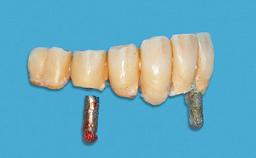

Improving an Existing Implant-supported Denture in an Alzheimer Patient with Bipolar Affective Disorder with Moderate Depression and Dementia

An 83-year-old man presented together with his caregiver at the dental department of the Medical University of Innsbruck, Austria with complaints of swelling in the right maxillary canine area and loss of retention of his 5-years-old mandibular denture. The patient had a significant medical history (20 years) of bipolar affective disorder with moderate depression (F 31.3) and dementia in Alzheimer’s disease (F 00.2). The patient had been in ambulant psychiatric therapy for his depressive illness for the past 20 years. He lived alone and had no children; his sister assisted with daily living. She reported that the patient exhibited compulsive hoarding behavior. In the previous two months, she had noted increasing disorientation and vertigo in the patient. She therefore accompanied him for a medical consultation at the Department of Psychiatry and Psychotherapy of the Medical University of Innsbruck. He was released home after a 6-week inpatient stay.

Prosthesis Type RDP